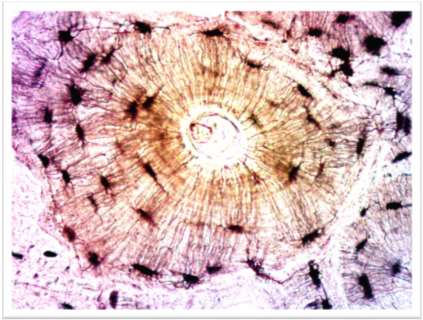

Osteon Structure in Compact Bone

The osteon is the fundamental structural unit of compact bone, designed to resist stress and provide strength.

Central (Haversian) Canal: Runs longitudinally, containing blood vessels and nerves.

Concentric Lamellae: Rings of calcified matrix surrounding the central canal.

Lacunae: Small spaces between lamellae housing osteocytes.

Canaliculi: Tiny canals radiating from lacunae, allowing nutrient and waste exchange between osteocytes.

Osteon Organization: The arrangement of osteons adapts to physical demands on the skeleton.